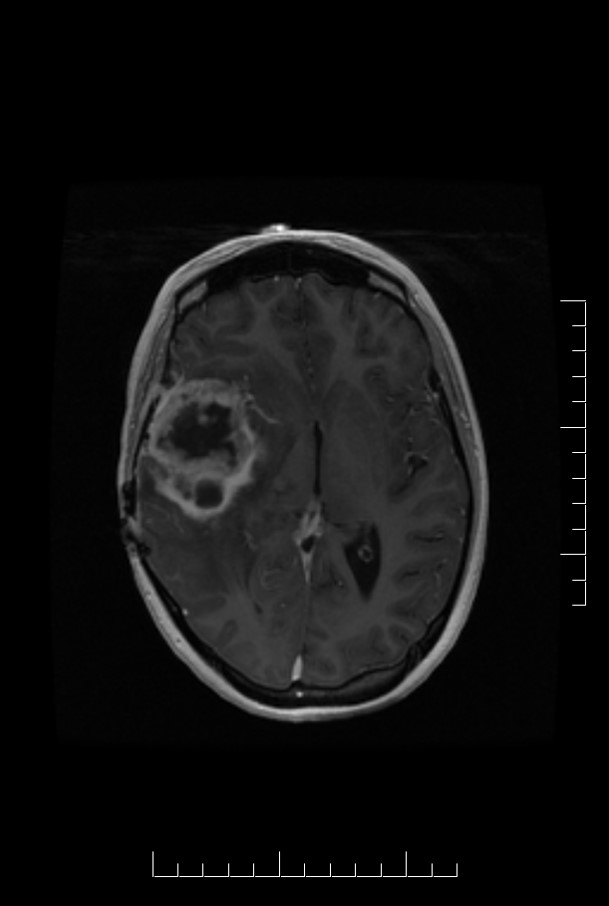

Case_4_T1C.jpg